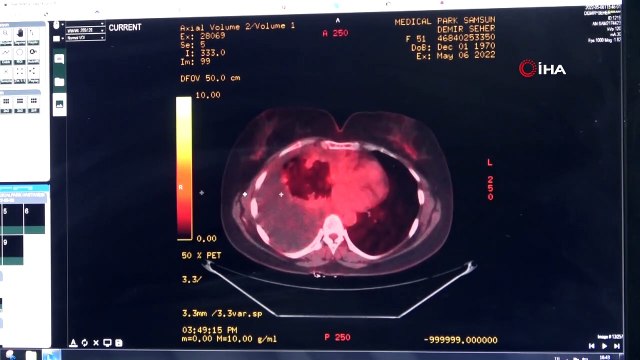

Yeşilay, gönüllüsü, gençler, vatandaşlara, balon, üfleterek, akciğer, kanserine, koah, hastalığa, dikkat, çekti